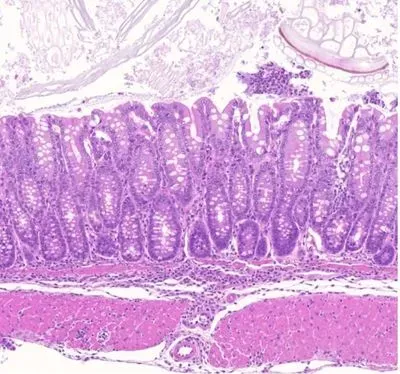

The researchers found that the enhancer element controls the expression of a gene in Treg cells, which encodes a protein called GARP (Glycoprotein A Repetitions Predominant). They showed that deleting this enhancer element caused loss of the GARP protein in Treg cells, and an uncontrolled response to a triggered inflammation of the colon lining. This demonstrated that the enhancer is required for Treg-mediated suppression of colitis, with a role for the GARP protein in this immune system control.